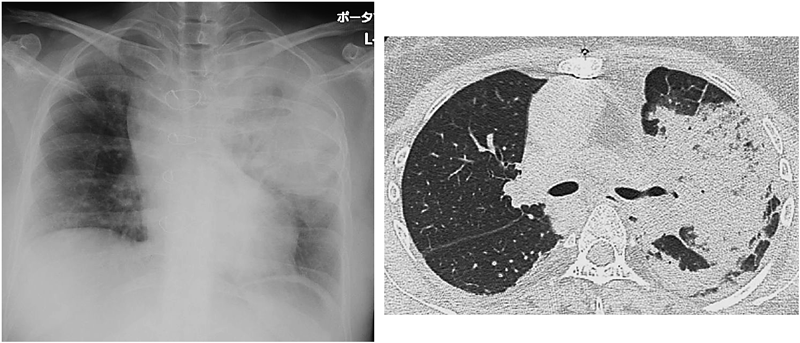

胸部X線,胸部単純CT(Fig. 1)では,左上葉の大葉性肺炎を認めた.肺の基礎疾患を疑う気管支拡張や嚢胞は認めず,胸水貯留は認めなかった.心電図(Fig. 2)は洞調律でST-T変化を認めなかった.心エコー図では,右側房室弁逆流を中等度認めるが入院前と著変なく,心収縮も保たれ壁運動異常は認めなかった.

Pediatric Cardiology and Cardiac Surgery 33(1): 50-57 (2017)

Fig. 1 Chest X-ray and chest CT on admission